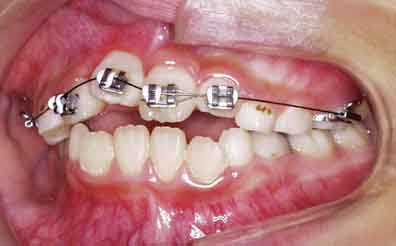

治療開始5ヶ月後